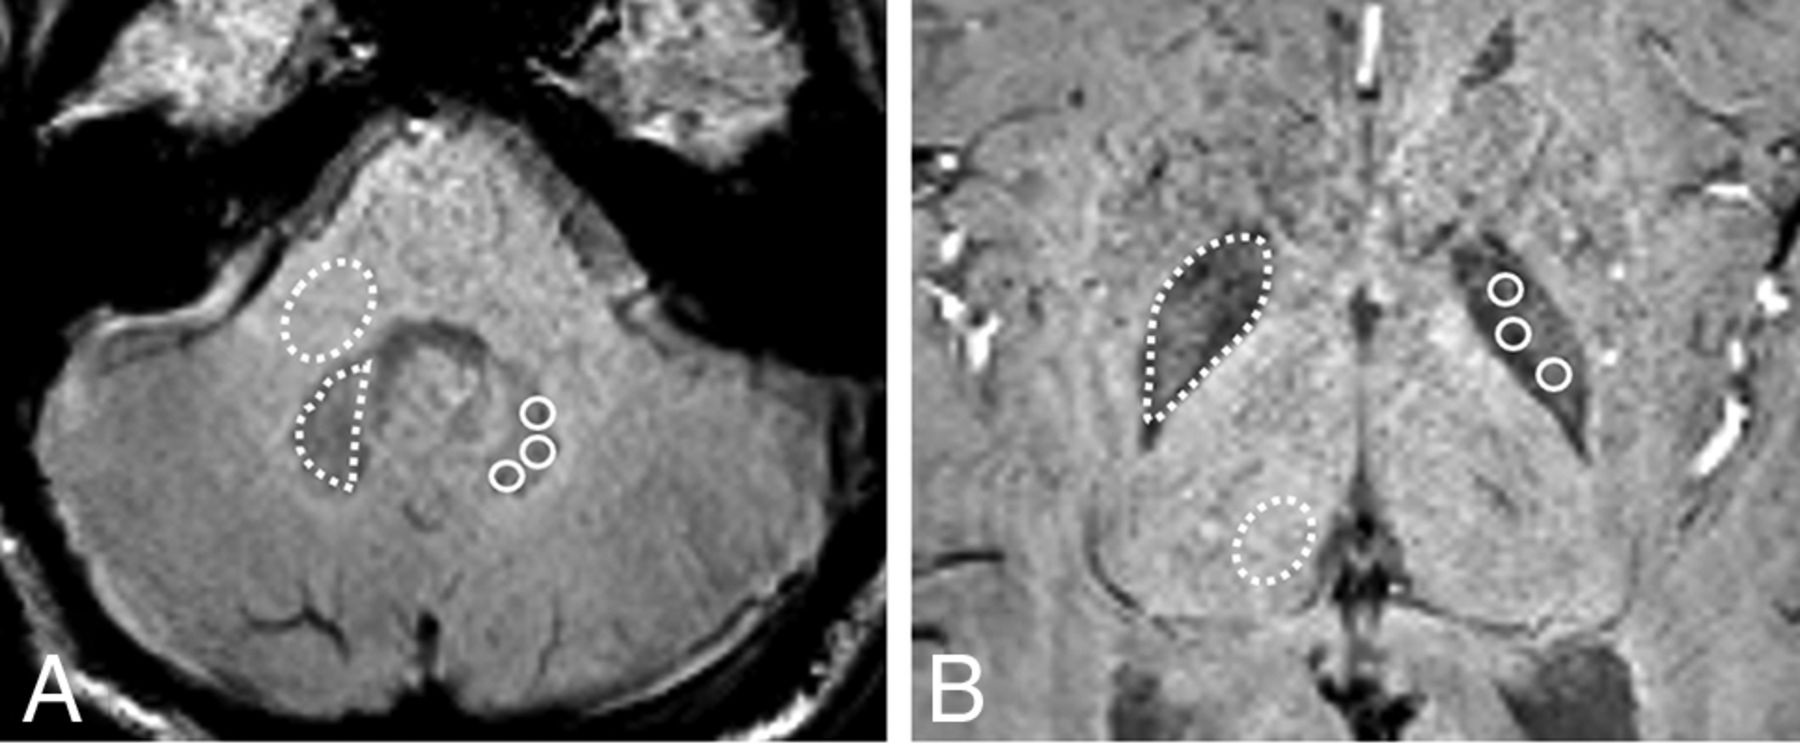

ROI placement and subsequent image-based analysis was performed using a dedicated software, Vitrea (Vital Images). Freehand ROIs were drawn within both the DN and GP; then, an elliptic ROI was placed in MCP and Th, respectively, on SWI to determine SWImean SI ratios with an average of 3 measurements. SWIminimum (min) was extracted from the manual placement of at least 5 circular ROIs into the DN and GP that encompassed 5 voxels (approximately 5 mm2), and the lowest value was determined (Fig 1). Compatible with the previous study,18 SI ratios were calculated as follows: T1WI ratio = (T1WI SI of DN)/(T1WI SI of MCP) or (T1WI SI of GP) / (T1WI SI of Th); SWImean ratio = (SWImean of DN) / (SWImean of MCP) or (SWImean of GP) / (SWImean of Th); and SWImin ratio = (SWImin of DN) / (SWImean of MCP) or (SWImin of GP) / (SWImean of Th). Eventually, all ROIs were visually inspected for correctness to modify possible structural displacement from baseline due to suboptimal coregistration.

SWI at the level of the DN (A) and GP (B) used for drawing the ROIs in the DN and GP with the corresponding MCP and Th for normalization, respectively. Dotted lines illustrate the freehand ROI used to obtain SWImean from the DN, GP, MCP, and Th; solid lines illustrate the circular ROIs used to obtain SWImin from the DN and GP.